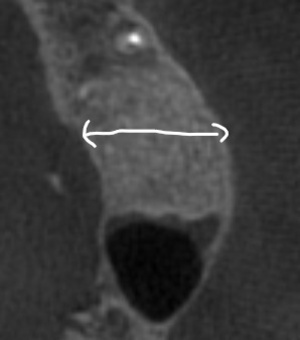

初診時(デンタル) 初診時(CT)

根管充填が不十分で、すき間もあり不良である

すき間なく緊密に根管充填されている

再感染リスクを抑える垂直加圧方式で充填しています(すき間が生じにくい)